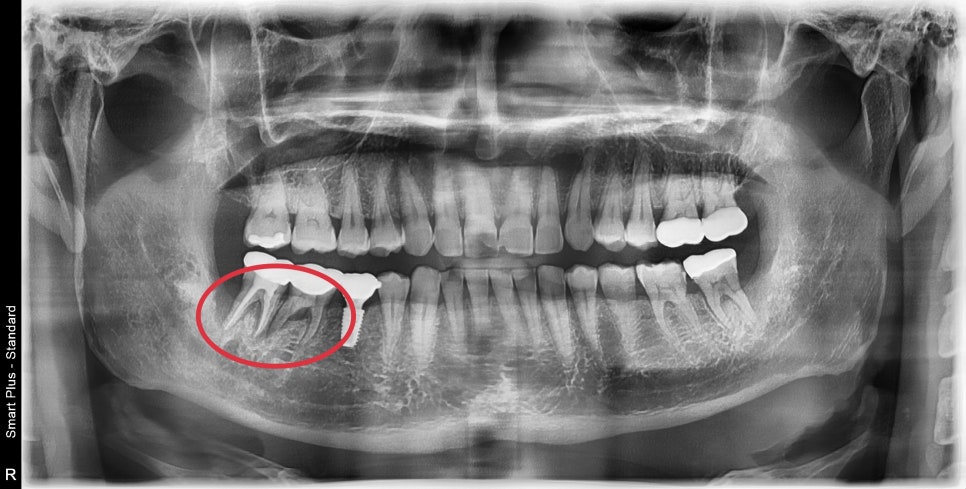

오른쪽 아래 어금니 두개가 흔들리고 부은채로 내원해주셨습니다.

엑스레이상에서 뿌리주변 뼈가 이미 흡수가 되어 동요도가 심한상태로

더이상 치아의 유지는 어려워 보였고 발치 및 임플란트 수술이 필요했습니다.